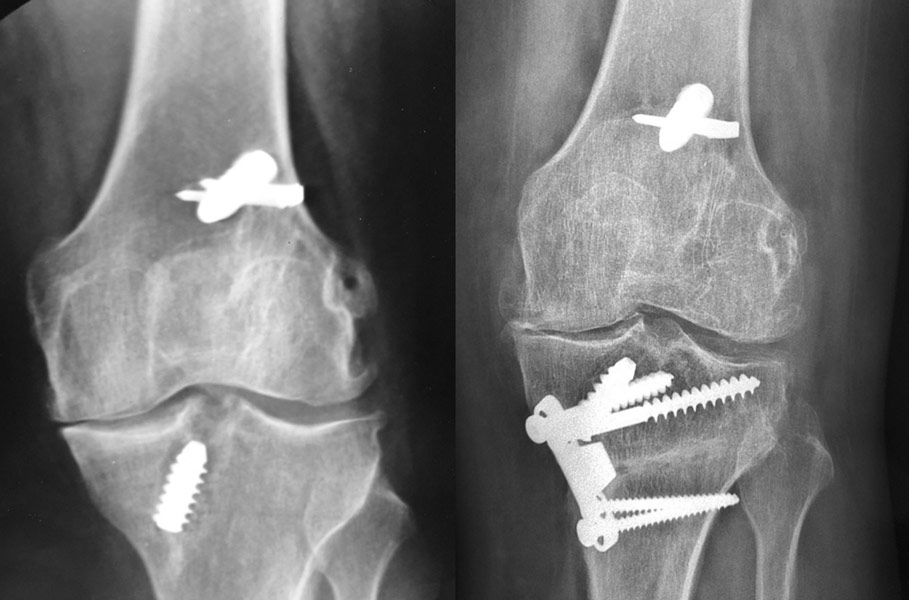

Patiente opérée à l’âge de 30 ans d’une rupture du ligament croisé antérieur. Arthrose progressive. Handicap important.

2ème opération à l’âge de 40 ans, du fait d’une arthrose interne du genou, par ostéotomie tibiale de valgisation. Excellent résultat 10 ans après

10 ans après l’ostéotomie, excellent résultat : aucune douleur, mobilités normales.